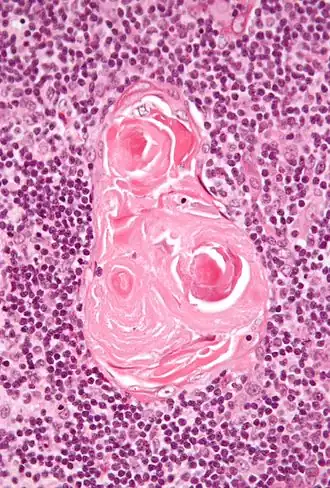

Micrograph of a thymic corpuscle; H&E stain.

Hassall's corpuscles (also known as thymic bodies) are structures found in the medulla of the human thymus, formed from eosinophilic type VI thymic epithelial cells arranged concentrically. These concentric corpuscles are composed of a central mass, consisting of one or more granular cells, and of a capsule formed of epithelioid cells. They vary in size with diameters from 20 to more than 100 μm, and tend to grow larger with age.[1] They can be spherical or ovoid and their epithelial cells contain keratohyalin and bundles of cytoplasmic fibres.[2] Later studies indicate that Hassall's corpuscles differentiate from medullary thymic epithelial cells after they lose autoimmune regulator (AIRE) expression.[3] This makes them an example of Thymic mimetic cells.[4] They are named for Arthur Hill Hassall, who discovered them in 1846.[5][6]